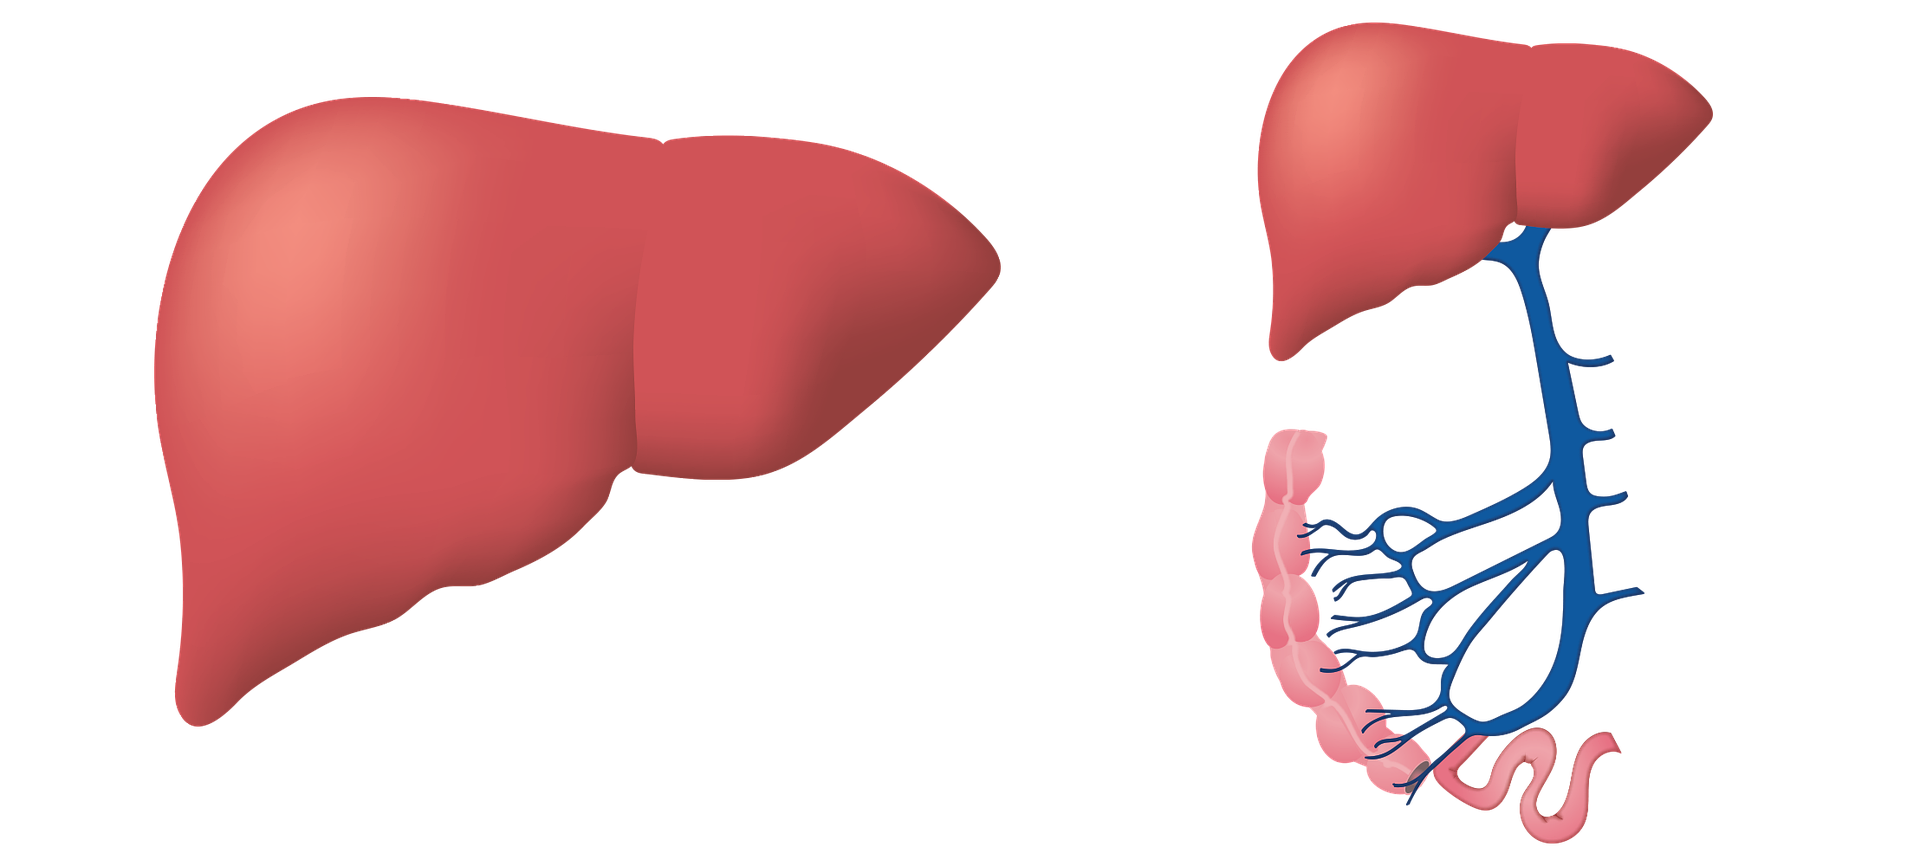

Hepatitis C causes liver inflammation. The virus can cause serious